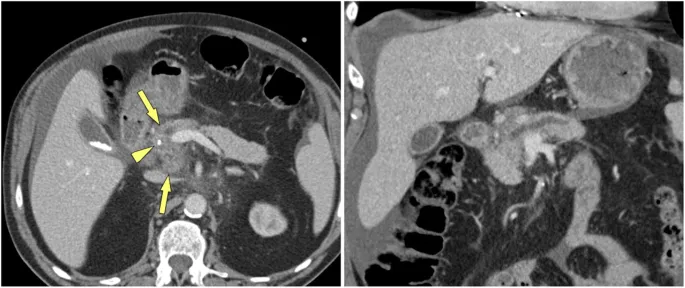

- CT Abdomen: Often the first-line imaging modality.

- Key findings: Pancreatic calcifications (pathognomonic), main pancreatic duct dilation (>3 mm), and parenchymal atrophy. Limited sensitivity for early disease.